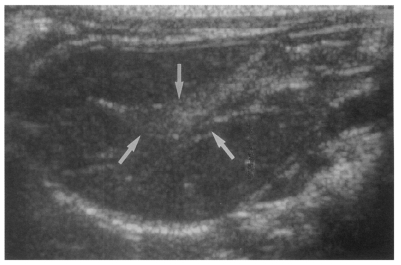

Sonography showed no dilatation of the bile duct confluence in the normal control group (Fig. 3). Sonograms showed moderate or marked dilatation of the bile duct confluence in the primary infection control group, the secondary infection control group, and the reinfection II group (Fig. 4, Table 2). A small number (1 of 7 in all groups) of animals showed mild dilatation of bile duct confluence in these groups (Fig. 5, Table 2). Dilated extrahepatic bile ducts were also observed. In the reinfection I group and the infection following immunization group, the degree of dilatation of the bile duct confluence was usually moderate (in n = 4 and n = 5, respectively). Marked dilatation was less frequent in these groups (n = 2 in each group).

High echogenicity closely packed at the dilated bile duct confluence was seen in all rats in the primary or secondary infection control groups; however, this was seldom noted in the reinfection I (n = 1) and reinfection II groups (n = 0) (p = 0.005 and p = 0.001, respectively) (Fig. 6). The echogenic mass was found to be composed of clusters of worms and desquamated materials by pathological examination. Small echogenic foci were noted in the dilated bile duct confluence in the infection following immunization group. These also represented worms and desquamated materials (Fig. 7). In the reinfection I and II groups, the degree of dilatation of the bile duct confluence on the last follow-up sonograms at 26 weeks after reinfection were noted to be slightly milder than those at 6 weeks after reinfection, but this was not significant (p = 0.266 and p = 0.431, respectively) (Table 2).

Fig. 5

Sonogram of a rat in the primary infection control group 4 weeks after C. sinensis infection, showing mild dilatation of the bile duct confluence (arrows).

kjp-42-7-g005.jpg